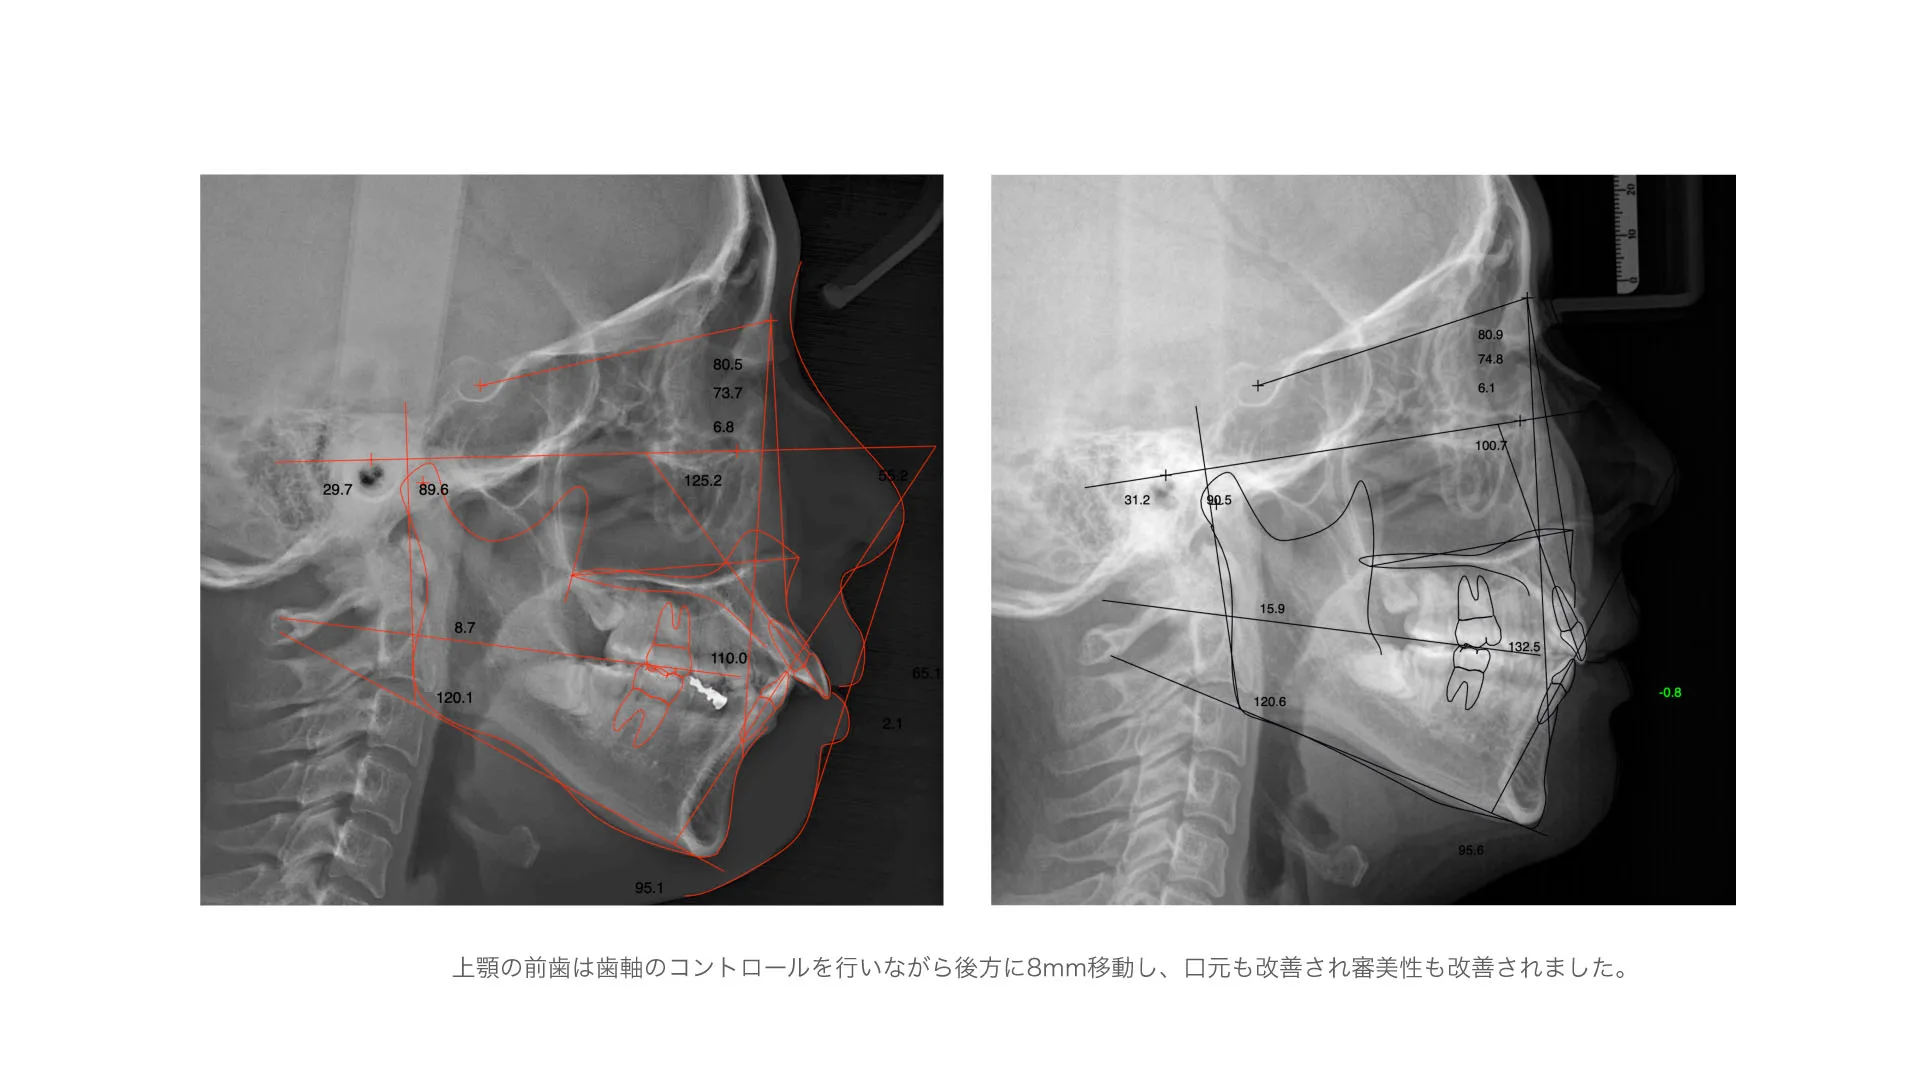

症例 口唇突出、正中離開